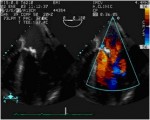

L’ Ecocardiografia rappresenta l’esame diagnostico principale per la diagnosi di insufficienza mitralica. Ci permette infatti la visualizzazione morfologica dell’apparato valvolare e delle camere cardiache, durante tutto il ciclo cardiaco, e quindi ci consente di valutarne lo stato e la funzionalità. Eseguita in prima istanza per via transtoracica (TTE) con la metodica bidimensionale è in grado di chiarire l’etiologia del rigurgito, mentre integrata con le metodiche doppler ci consente di quantificarlo.

L’area del jet di rigurgito, esaminata al color-doppler , è uno dei parametri più usati, soprattutto quando espressa in rapporto all’area dell’atrio sinistro.

Il diagramma mostra la valutazione della severità dell’insufficienza mitralica usando l’approccio transesofageo con vista asse-lungo. La gravità dell’insufficienza mitralica (1-4+) viene stabilita in base alla lunghezza e alla larghezza del flusso di jet nell’atrio sinistro. LA, atrio sinistro.; RV, ventricolo destro; LV, ventricolo sinistro.

ecocardiografia.jpg

Immagine16.jpg